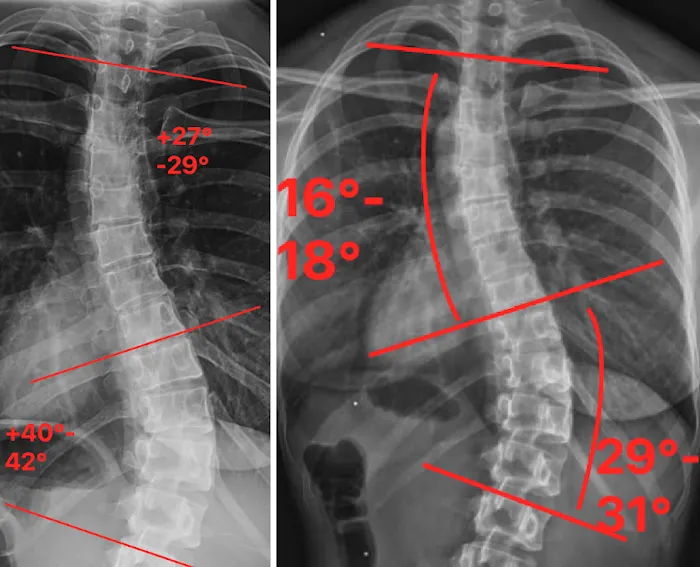

The philosophy at the Scoliosis Correction Center is built on a deep understanding of spinal biomechanics and a commitment to non-surgical intervention. Scoliosis, a condition characterized by a lateral curvature of the spine, can cause a range of issues, from back pain and postural imbalances to reduced mobility. The center’s approach is to provide a conservative, gentle, and effective alternative to surgery. They utilize a variety of specialized chiropractic techniques and rehabilitative exercises designed to correct spinal curvature, strengthen supporting muscles, and improve overall spinal health. This focused expertise is a significant advantage, as it allows the team to develop highly personalized and targeted treatment plans for each patient's unique curve and condition.

- Scoliosis Correction Programs: The primary service of the clinic, these programs are designed to reduce the curvature of the spine, improve posture, and alleviate associated pain without the need for invasive surgery.

- Non-Surgical Spinal Care: The center provides a conservative and gentle approach to spinal health, utilizing specialized chiropractic adjustments and techniques tailored to the unique needs of scoliosis patients.

- Personalized Treatment: The team understands that no two spines are alike. They create individualized treatment plans based on a thorough examination and a detailed understanding of a patient's specific spinal curve.